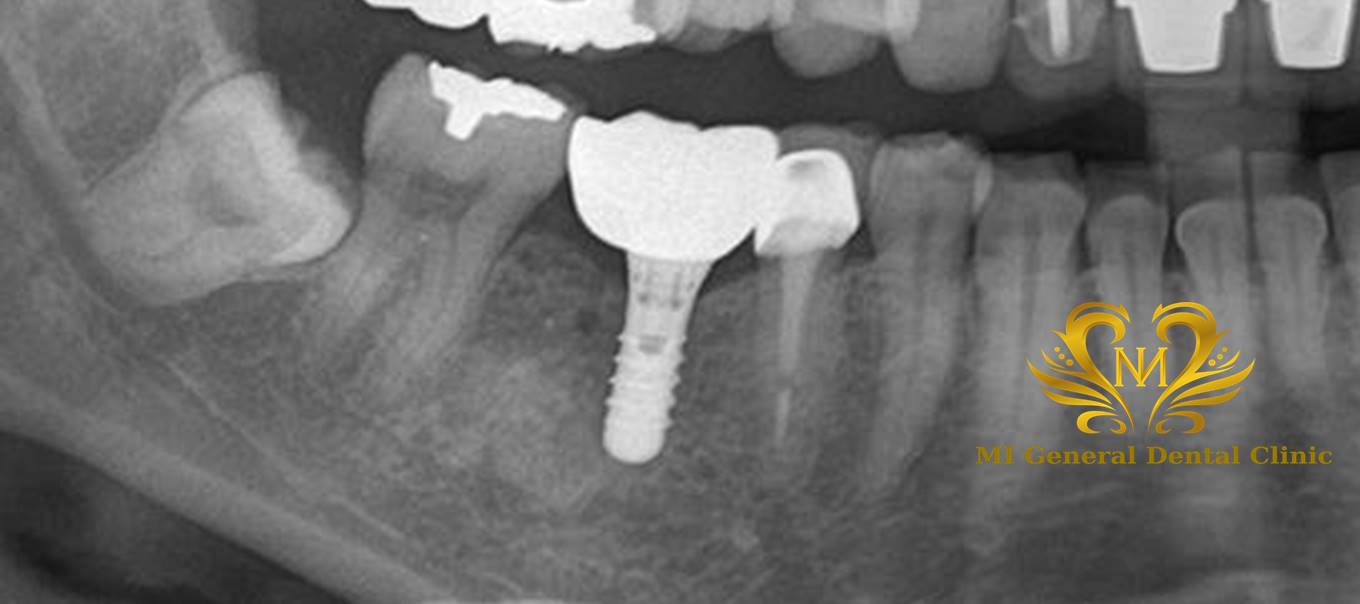

治療後

インプラント治療及びセラミックスによって咬合回復しました。

インプラント体が入りしっかり噛むことが出来ます。

欠損補綴の説明(インプラント、ブリッジ、入れ歯)をし、インプラント治療を希望された為、右下の奥歯にインプラント体埋入後に、骨とインプラント体の定着を待ちセラミックスを被せました。